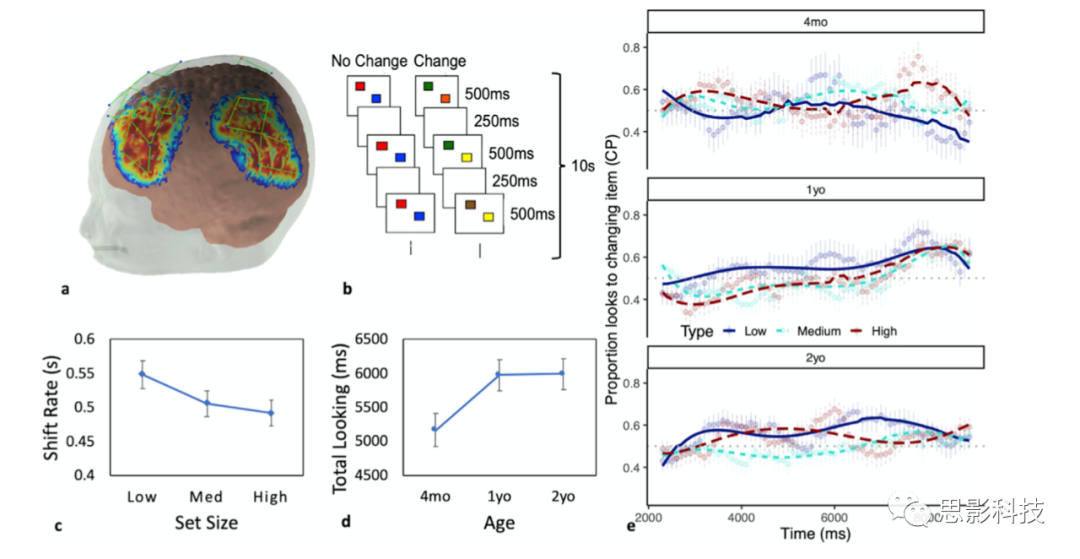

8、NeuroImage 两岁前儿童视觉工作记忆的基础是功能性脑网络

视觉工作记忆(VWM,Visual working memory)是一种用来比较世界观和检测局部环境变化的中枢认知系统。这一系统在生命的前两年发展变化巨大。然而,我们对VWM在大脑层面的功能组织知之甚少。来自东英吉利亚大学的Reyes等人,在NeuroImage发文,使用功能性近红外光谱(fNIRS)技术,在77名婴儿中采集了19个皮层感兴趣区域(根据成人VWM相关文献选取)的神经活动,以探索VWM网络在早期发展中的空间组织。

结果显示,19个ROI中的6个有显著的任务特异性功能激活,本研究中激活的脑区和在成人fMRI研究中被确认为VWM网络的部分脑区存在空间一致性。工作记忆相关激活主要集中在双侧前顶叶内沟(aIPS)、左侧颞顶交界(TPJ)和左侧枕腹复合体(VOC)上,而视觉探索与右侧背外侧前额叶皮层、左侧TPJ和双侧IPS的激活有关。本研究的结果表明,一个分布式的脑网络是婴儿期VWM功能变化的基础。

原文:The functional brain networks that underlie visual working memory in the first two years of life

DOI:doi.org/10.1016/j.neuroimage.2020.116971